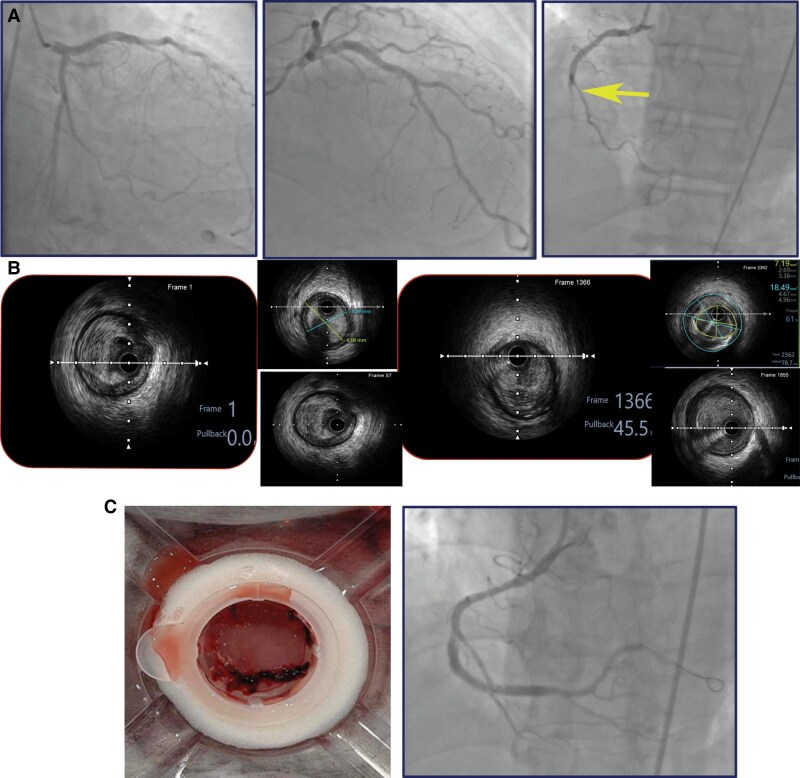

Case summary: We report a case of a 67-year-old male presenting with acute ICH who subsequently developed inferior STEMI complicated by third-degree atrioventricular block. The patient underwent a deferred percutaneous coronary intervention (PCI) strategy, involving only balloon angioplasty and thrombectomy without stent placement, to restore coronary flow while minimizing the risk of exacerbating the intracranial haemorrhage. Three days later, ischaemia progressed to recurrent myocardial infarction, at which point reassessment revealed stabilization of the ICH, allowing for stent placement in the right coronary artery (RCA) and the administration of antithrombotic therapy.

Discussion: The deferred PCI strategy, involving initial thrombectomy and balloon angioplasty without stent placement, facilitated temporary restoration of coronary flow and provided a critical time window for the stabilization of the ICH. This approach enabled subsequent stent implantation and the reintroduction of antithrombotic therapy (anticoagulants and antiplatelets). This strategy demonstrates its effectiveness in managing patients with concurrent STEMI and ICH by balancing the risks of ischaemia and haemorrhage, thereby improving clinical outcomes.